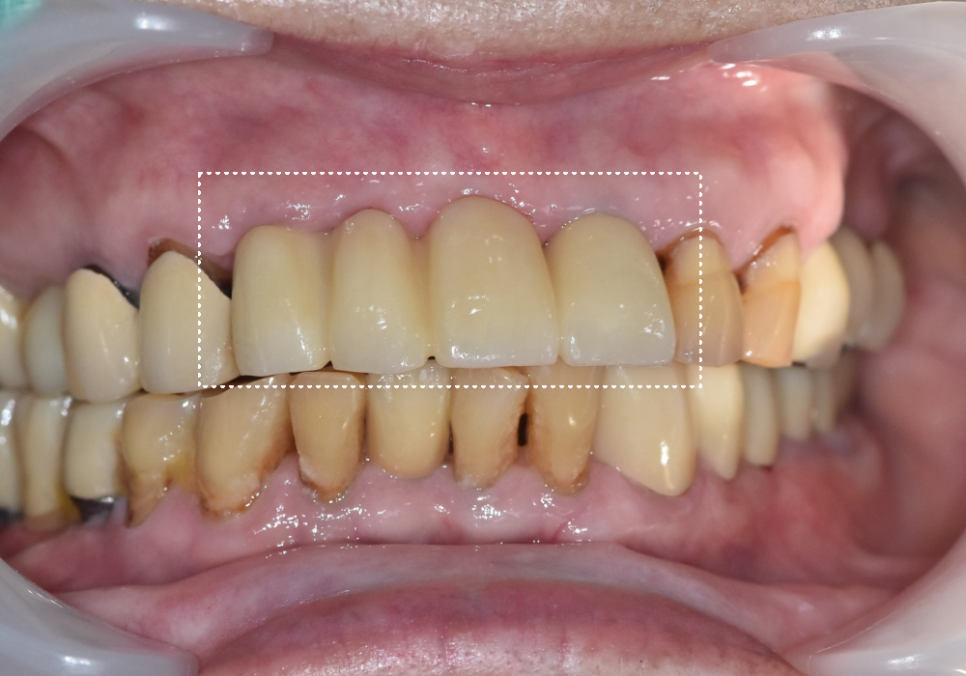

250510

그래서 동일하게

발치 후 임플란트로 진행했고,

이 역시 약 3개월 뒤 보철을 완성했습니다.

250728

231109 (전) 251108 (후)